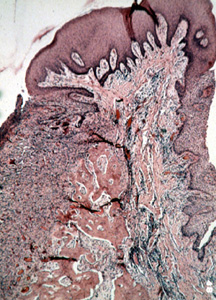

Esta microfotografía de baja resolución muestra  varios componentes del tejido. Hay áreas de tejido conjuntivo celular y zonas de inflamación crónica. Además, usted puede ver las numerosas trabéculas óseas que a  menudo están presentes.

Ilustrado aquí es el área central de tejido conjuntivo celular con el epitelio encima y trabéculas de hueso al fondo. La presencia de hueso es común.